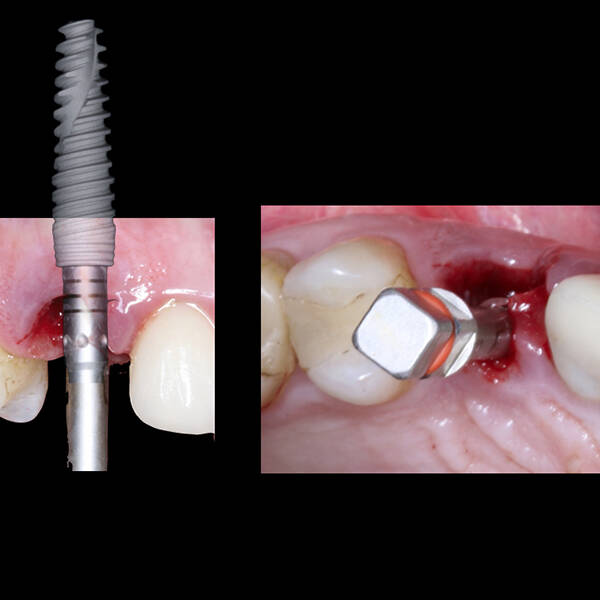

- Planejamento Digital: Com o auxílio de tecnologias como tomografias e softwares 3D, a posição dos implantes é planejada com precisão.

- Cirurgia de Instalação dos Implantes: Os implantes são fixados no osso maxilar ou mandibular, proporcionando uma base sólida para a prótese.